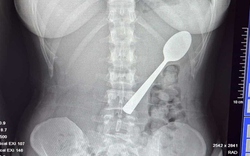

• Đang ăn sữa chua, người phụ nữ nuốt chiếc thìa dài 17cm vào bụng

Đang ăn sữa chua, người phụ nữ nuốt chiếc thìa dài 17cm vào bụng

Một người phụ nữ đã vô tình nuốt phải một chiếc thìa dài 17cm khi con chó của cô nhảy lên đùi trong lúc cô đang ăn sữa chua.